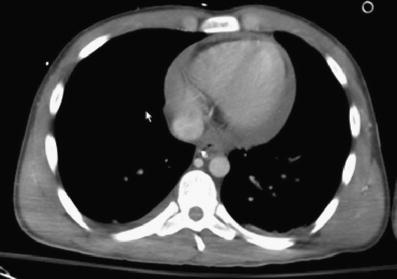

Fig. 2

Abdominal CT image at the renal level shows periportal edema, ascites, IVC and right renal vein enlargement